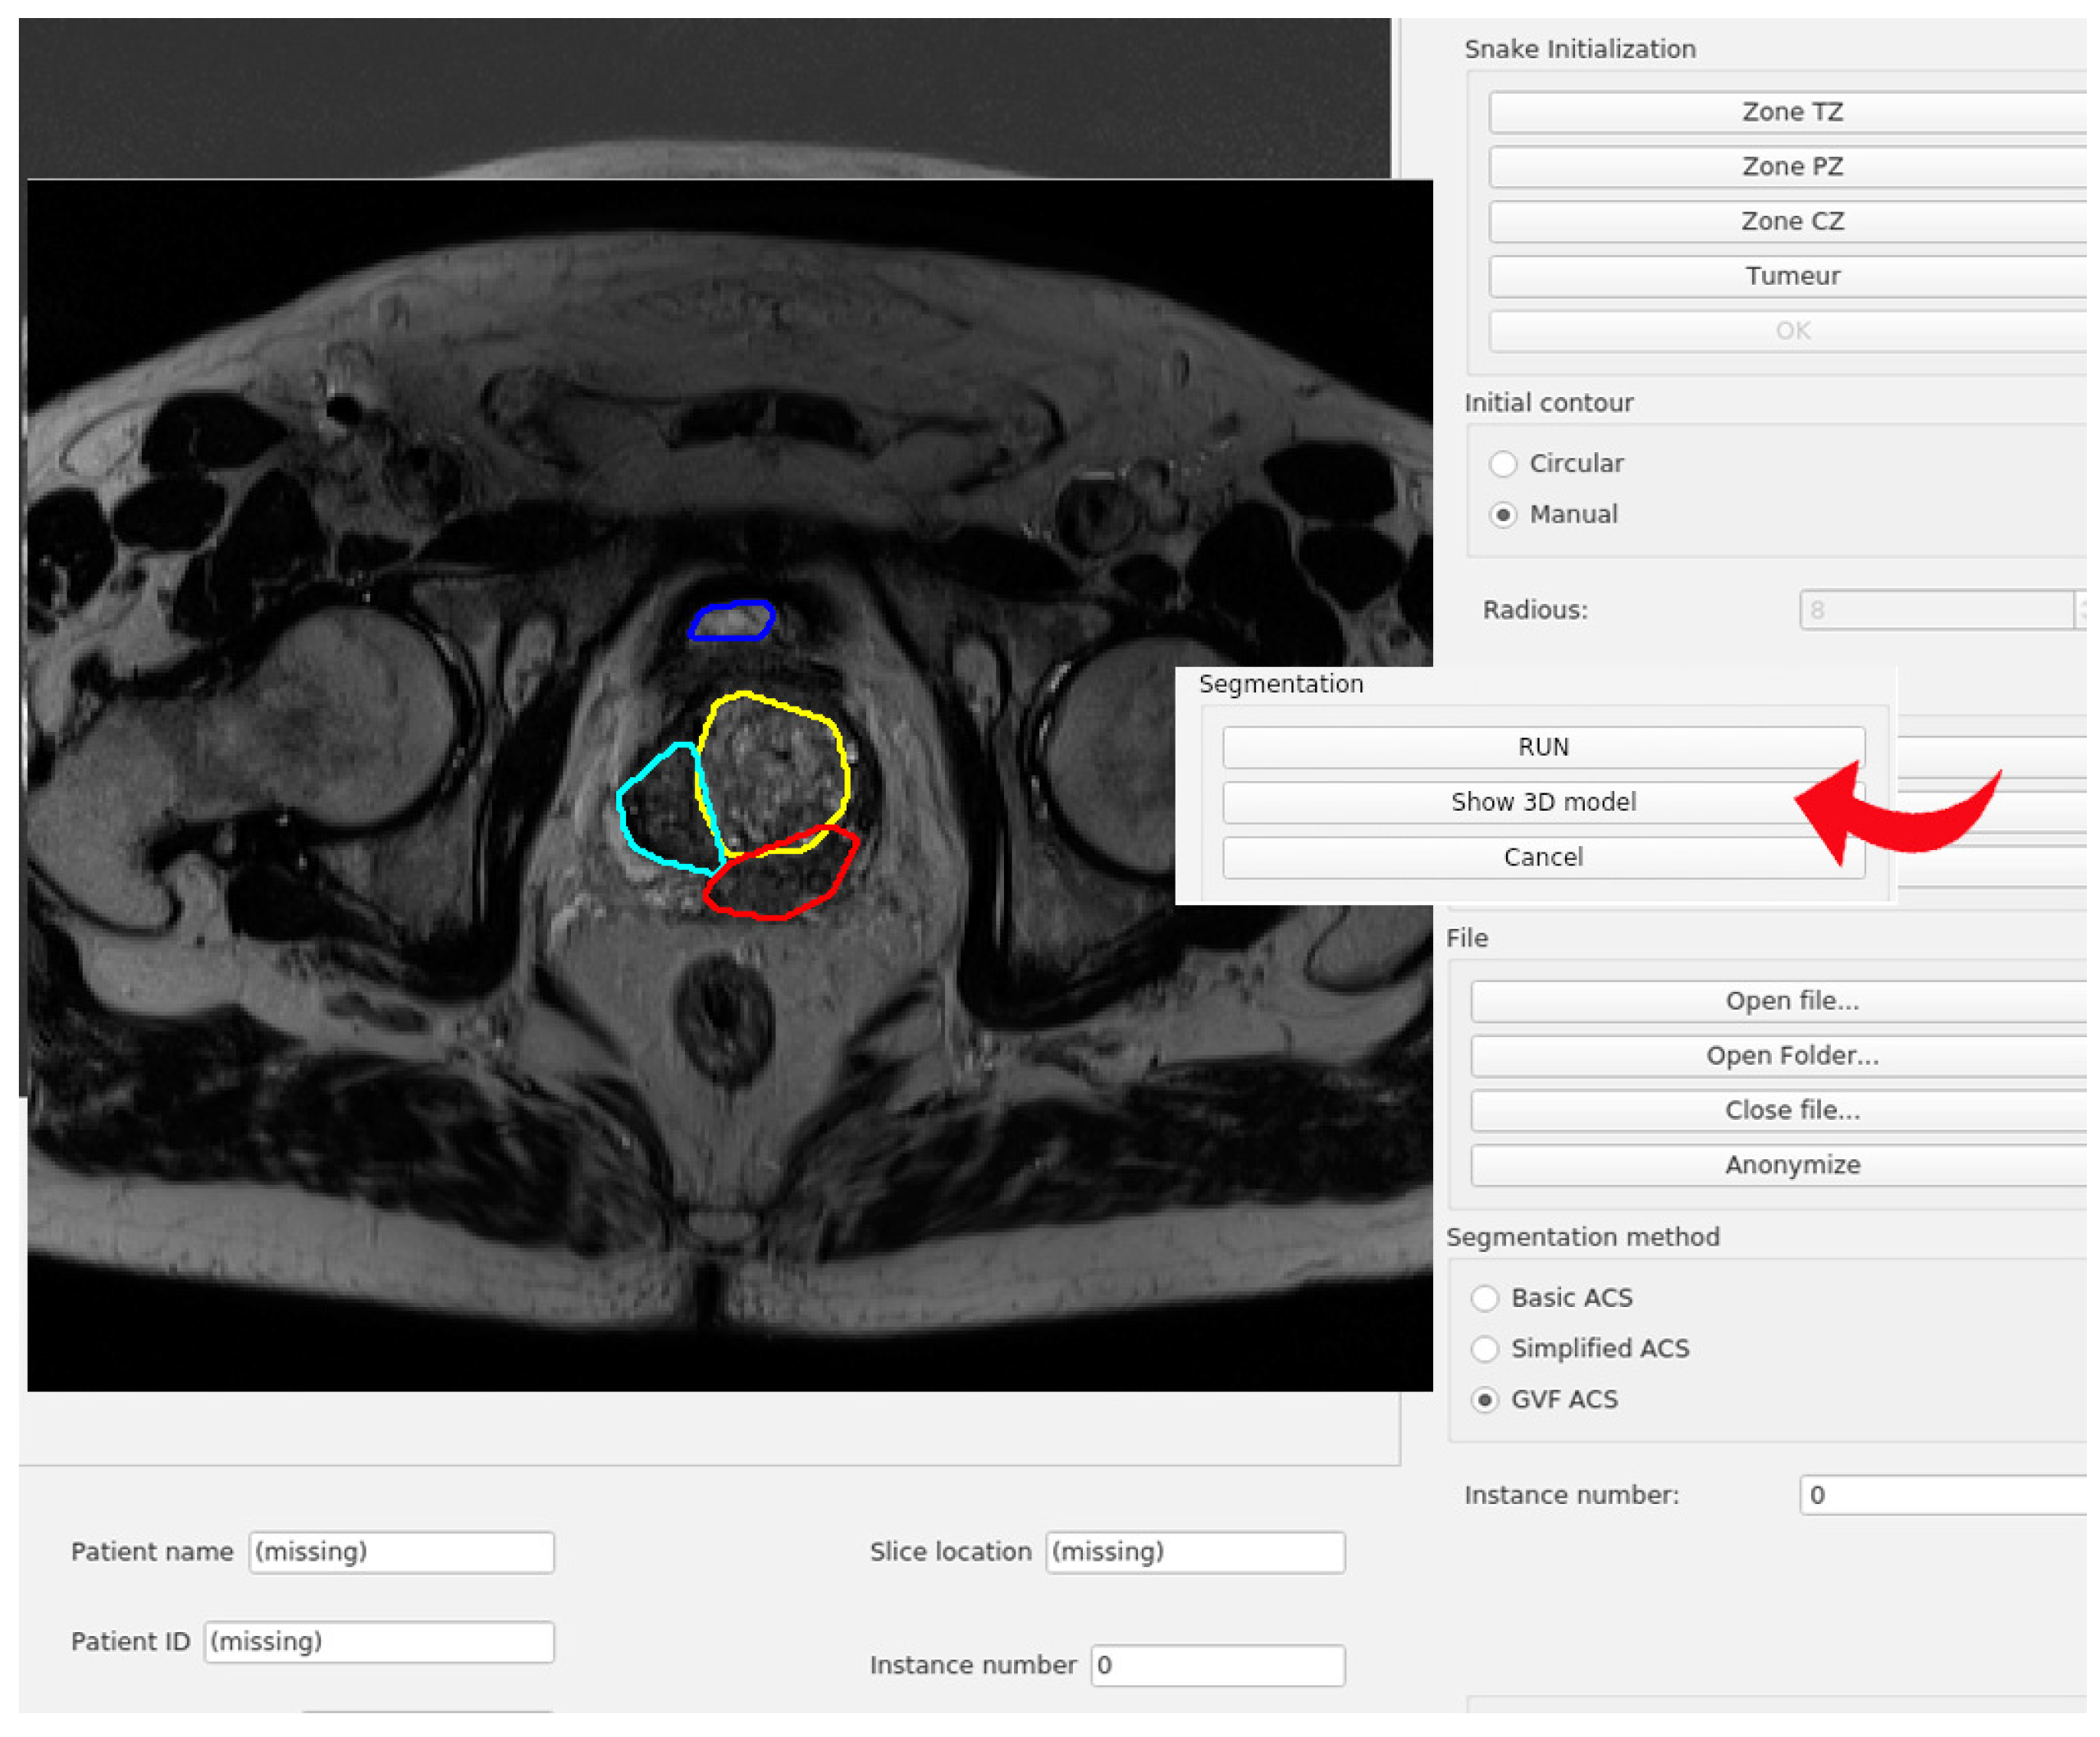

In this section, the code organization and the user interface of the program will be explained. The main window of the program is shown in Figure 3. All the code has been developed in Python, using the modules PyQt for the user interface and PyDicom to open the files included in the testing dataset. The code has been organized in modules that do not interact with each other. The integration of all of them has been made in the Main Window class.

The data available to the user includes the images and the patient data fields. This module is also in charge of anonymizing the files and writing them into disc. The functionalities of this module can be accessed through the buttons in the Section 1 of the Figure 3.

• Image segmentation. This module stores all the Python code related to the segmentation procedure. The main class in this module is Segmentation-Hub, which is in charge of selecting the right class for the object that will produce the segmentation, according to the method chosen by the user. The selection of the segmentation method can be done in Section 2 of Figure 3. By implementing the methods in this manner, the actual implementation of the segmentation task is completely transparent for other classes that make use of this module. To select certain segmentation method, only a label that defines the method must be provided.

• Image widget. This module is in charge of showing the image, as well as the initial and the resulting contours from the segmentation. The same module is used for both, left and right images. It also captures the clicks from the user to generate either the circular or the manual initial contour. Both types of initialization will be explained later. The image widget is represented in Sections 3 and 4 of Figure 3.

• Model 3D widget. It shows a 3D representation of the output segmentation, based on the Python module Matplotlib. This process is relatively simple as it only replicates the given contour vertically. If the spatial resolution is given in the input DICOM file, the scale of the axis will be given in millimeters. It can be accessed through the button S h o w 3 D M o d e l located in Section 5 of Figure 3.

• Snake init widget. This widget is in charge of handling all the functionalities of the Snake initialization group, placed at the top of the central control panel of the application.

Afterwards, the corresponding masks for those contours can be generated for the snake algorithm (the mask consists of an image with values of 1 in the interior of the contour, and zeros outside of it). The interface for this module is represented in Section 6 of Figure 3.

• User data widget. It is implemented as an efficient and easy to use manner to handle all the user information as an object, and to show it. This class stores all the information related to the patient or the study, retrieved from the DICOM file. It also contains the corresponding widgets that are shown below the left image area, where the gathered information is displayed (see Section 7 of Figure 3).

Finally, regarding the user interface showed in Figure 3, this program has four well-defined sections:

• Left panel. In this area (highlighted in blue), the loaded images are shown, and the user can draw the initial contours of the snake of the different areas of the prostate. Each prostate zone is surrounded with a different color to make it easily distinguishable (see Figure 3)

• Right panel. This area (highlighted in orange) shows the loaded images, and the results of the evolution of the selected snake algorithm. Each prostate zone has a pre-defined color, and they match with the colors used for the initial contours (see Section 4 of Figure 3).

• Bottom area. The patient information retrieved from the DICOM file is shown (highlighted in blue). Moreover, information related to the spatial resolution and thickness of the gathered slice are included (Section 7 of Figure 3)

• Central area. This is the control panel area (highlighted in green). All the functionalities and possible configurations of the program are located in this area. It is represented in the Sections 1, 2, 5 and 6 of Figure 3.

First, the user must load an image in DICOM format. For this application, the snake initialization is required; an example of the initial contours for a study is shown in Figure 8. In the area of the GUI that corresponds to the initialization of the snake, the three first buttons are used for selecting the different zones of the prostate, whereas the fourth one gives the possibility of selecting a tumor.

The following area of the control panel is used for triggering the segmentation. This section is depicted in Figure 9. After an image has been loaded, at least one initial contour has been entered, then the segmentation process will start after pressing the R u n button. The segmentation method will be triggered as many times as initial contours have been entered, and they will be executed sequentially. During this process, the user can cancel the segmentation at any moment, pressing the C a n c e l button. Once the algorithm had finished, the results will be shown in the right image. Additionally, the color code of the contours is the same for both, left and right images. For instance, the resulting contour of color blue in the right image has as initial contour the blue snake from the left image.

Figure 3. GUI interface of the developed active contour segmentation tool using a prostate MR image.

Figure 9. Example of snake results after the snake segmentation.